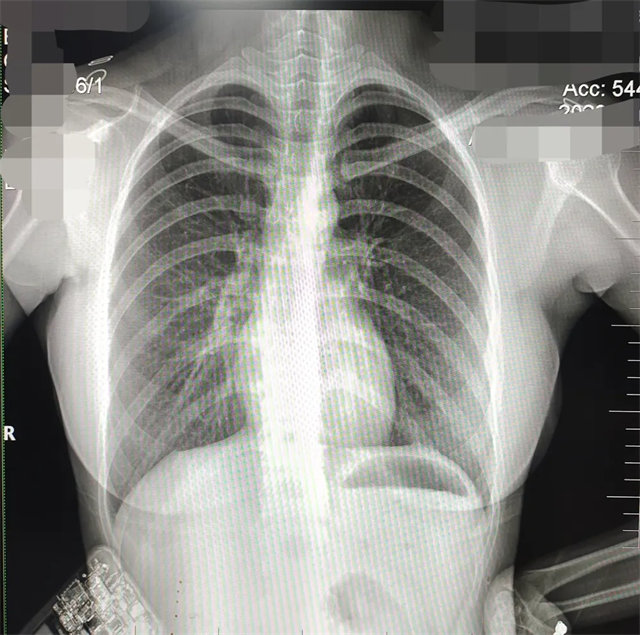

缺陷:两肩胛骨未拉开肺野之外,吸气不完全,且存在金属饰品遮挡。

解决:去除金属饰品及内衣后重新按标准体位摄片即可。